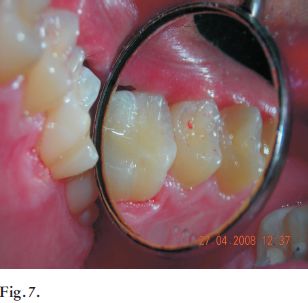

Concomitantemente, Pitts (1) en 1990 afirmó la dificultad que existe de identificar lesiones de caries que involucran tejido dentinario, por el método de inspección visual. Por eso el autor aconseja el uso de radiografías interproximales como complemento en el diagnóstico en la determinación de lesiones que comprometen la dentina, justamente cuando se requiere de tratamientos invasivos (Figs.3, 4 y 5).

Figs. 3, 4 y 5. Se aprecia una lesión cariosa aparentemente incipiente en la pieza 37. En la radiografia se visualiza gran afectación dentinaria, que se correlaciona con la clínica una vez realizada la apertura.

Fig. 6 y 7. Preparación dentaria en una lesión incipiente y su restauración con resina compuesta.